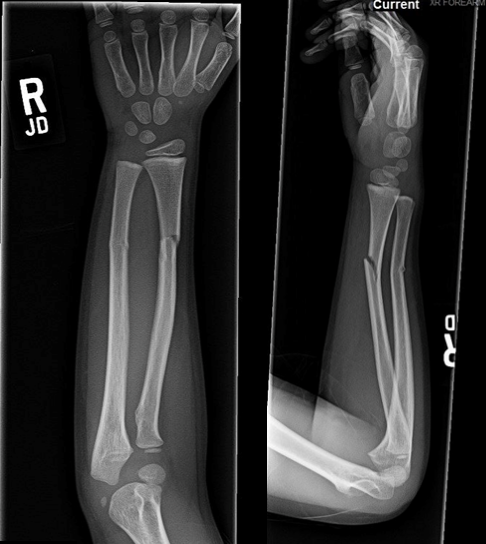

5

Q

What is the diagnosis for the fracture of the radius and the causative mechanism?

A

Greenstick fracture

Angular/shear force (bending)

How well did you know this?